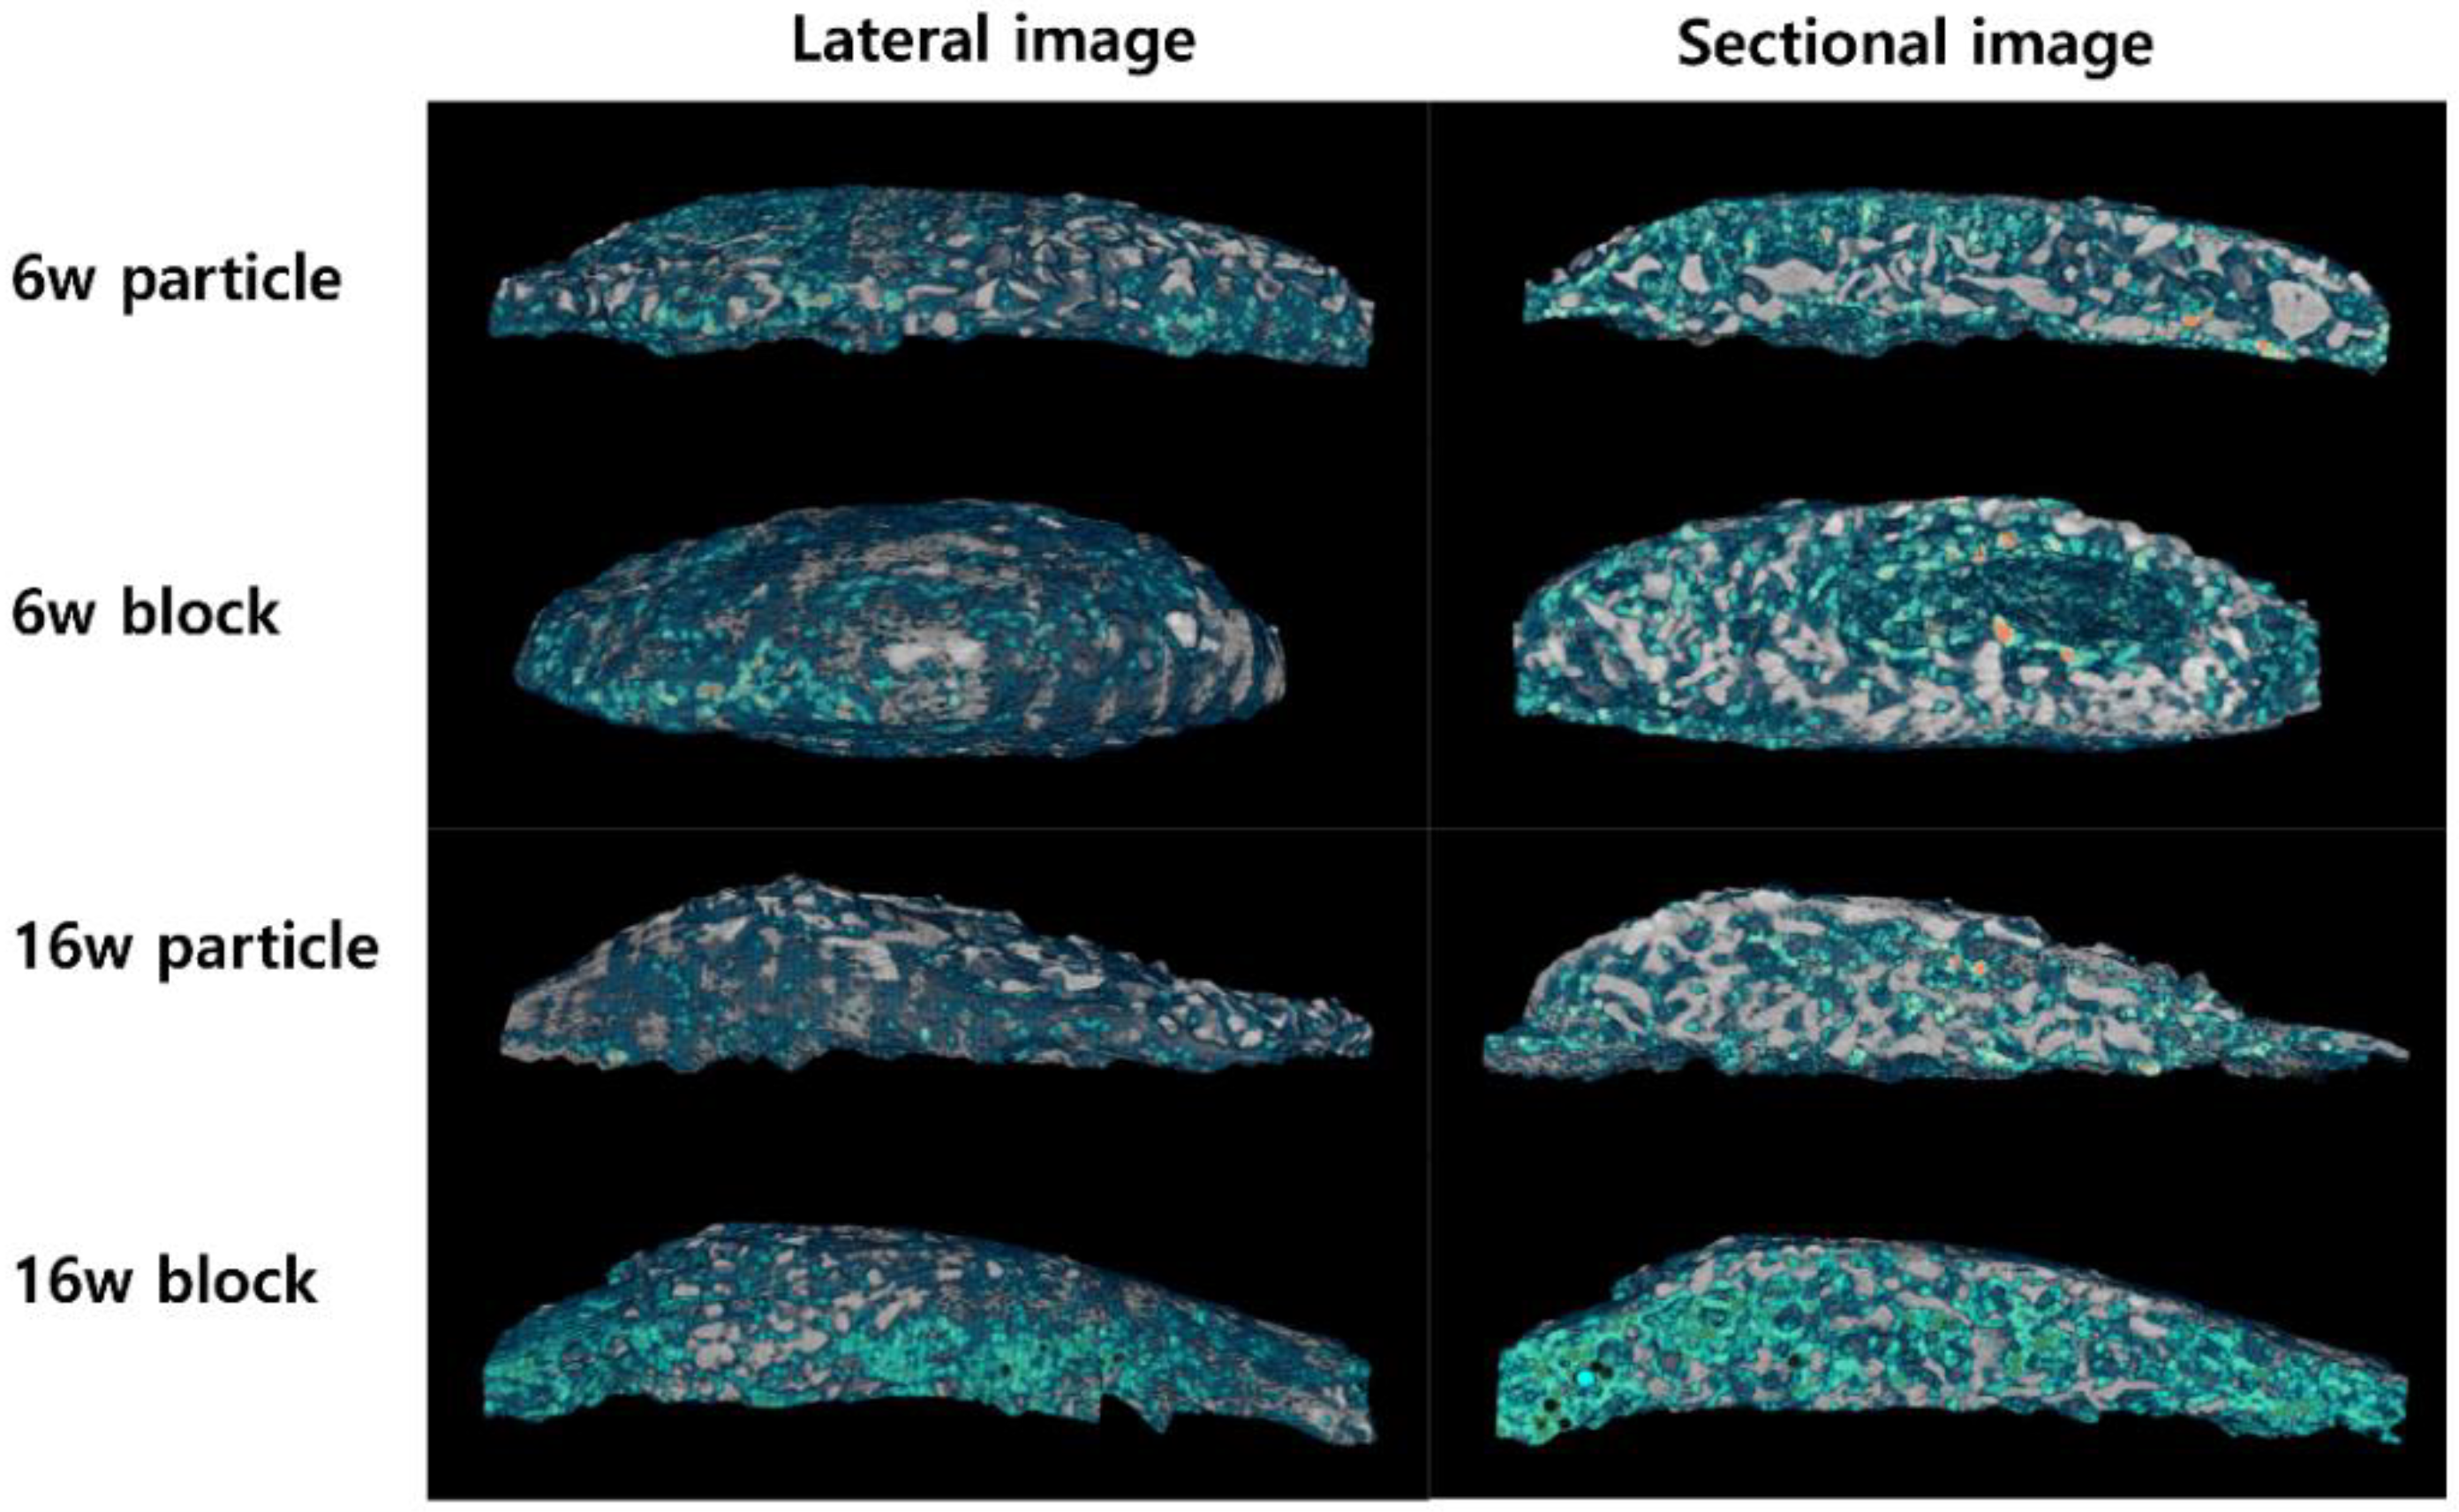

3.2. Changes in Adipose Tissue in the Newly Formed Bone